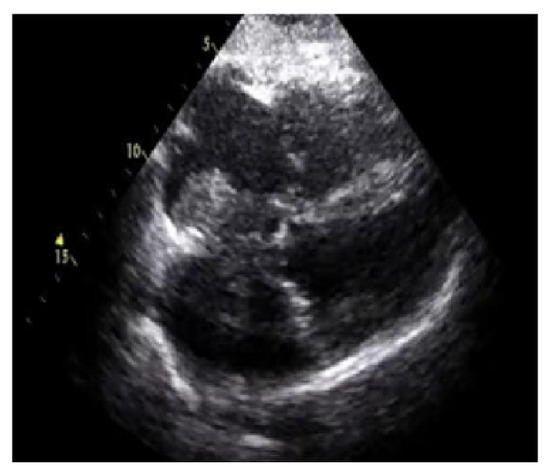

The numerical outcomes of the proposed as well as existing techniques are presented in this section. The input image of echocardiograms is given in Figure 4, and the pre-processed image is given in Figure 5. The FCM based segmentation is accomplished in echo images that is illustrated in Figure 6.

Figure 4.

Input image.